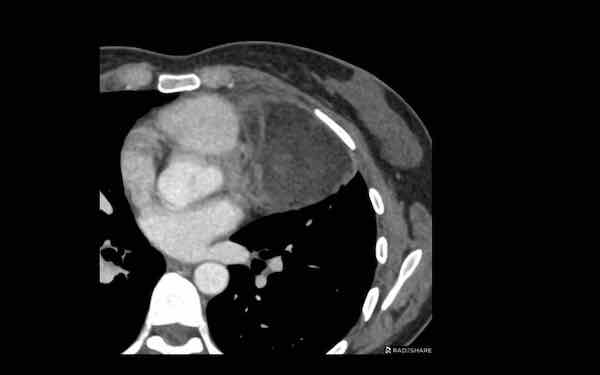

Các hình ảnh này của một bệnh nhân nam 68 tuổi, vừa trải qua phẫu thuật bắc cầu động mạch vành.

Bệnh nhân than phiền khó thở.

Nồng độ D-dimer cao và CT được thực hiện để tìm kiếm thuyên tắc phổi.

Hình ảnh

Có một khối trong trung thất trước mạch máu.

Tỷ trọng là 44